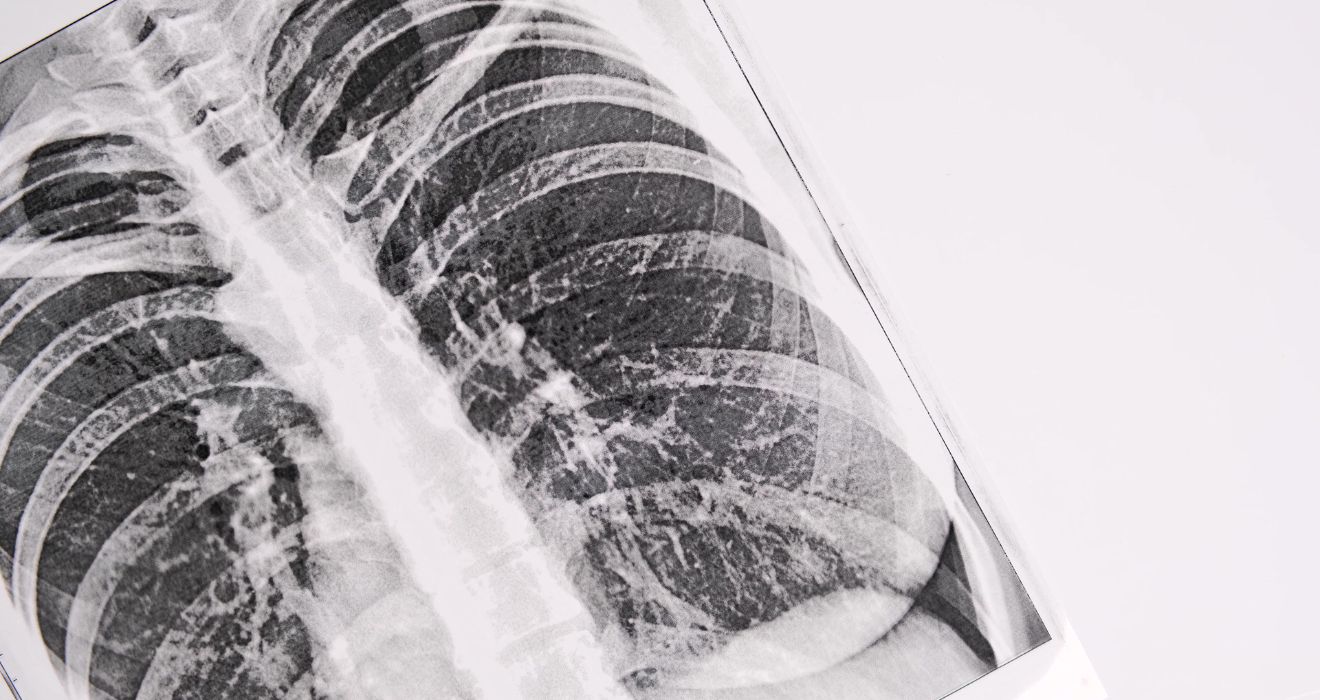

• Chest X-ray & HRCT